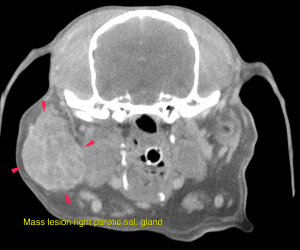

A well-defined, ovoid mass lesion with lobulated appearance and undulating surface is seen in the area of the right parotid salivary gland, measuring 3.8 x 3 x 3.5 cm in size. After contrast administration the mass lesion presents moderate irregular contrast enhancement with multiple spherical non-contrast enhancing areas. The right superficial cervical lymph node is prominent and presents a moderate increased short-to-long-axis ratio of 0.5. The right thyroid gland presents severe enlargement at 2.4 x 2.4 x 2.8 cm. The regular parenchyma is completely displaced by ill-defined moderately contrast enhancing tissue with multiple spherical non-contrast enhancing areas. At the level of the neck the tracheal rings are mildly flattened and the luminal diameter is reduced.

Differential diagnosis for the salivary gland mass includes primary soft tissue neoplasia (fibrosarcoma) with invasion of the parotid salivary gland or – even though rare in canine – primary neoplasia of the parotid salivary gland (such as adenocarcinoma or less likely adenoma).For further workup – if not performed yet – FNA samples or biopsy are essential. Surgical excision is advised. The right thyroid gland presents a mass lesion compatible with primary neoplasia. Possible differential diagnosis are cystic adenocarcinoma or less likely adenoma. In dogs these are rarely functional. Surgical removal of the right thyroid is the therapy of choice. FNA samples from the right superficial cervical lymph node are essential prior to surgery for complete staging. The findings of the right adrenal gland are consistent with primary neoplasia. Possible differentials include functional/non-functional adenoma or adenocarcinoma, pheochromocytoma. Invasion of the phrenicoabdominal vein is likely, invasion of the caudal vena cava cannot be ruled out. The potential of vascular invasion increases the odds of a primary malignancy.